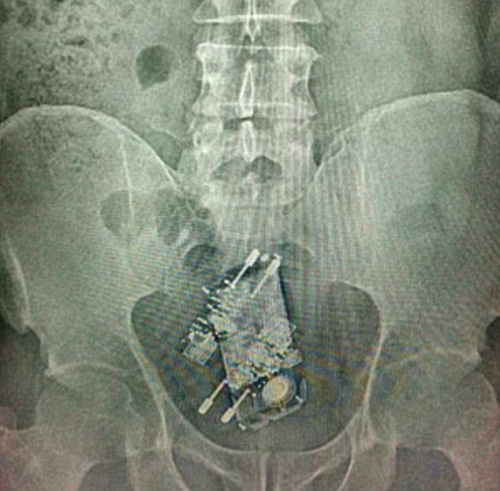

Hình ảnh chụp X - Quang điện thoại và 2 cục sạc trong bụng của người tù Brazil |

Các viên cai ngục cho biết, hôm qua 14/10, các tù nhân được phép ra ngoài trong một khoảng thời gian nhất định để ăn mừng ngày Tết Thiếu nhi, và rồi họ phát hiện bên trong dạ dày của một tù nhân có 1 điện thoại, 2 cục sạc sau khi anh ta quay lại.

Trở lại sau khi ra ngoài, các tù nhân đều được quét X – Quang qua cửa an ninh, vì vậy ban quản lý nhà tù mới phát hiện ra vụ việc hi hữu này. Ngay sau đó, anh ta được đưa tới bệnh viện địa phương để bỏ hết các vật dụng gây hại này ra ngoài.